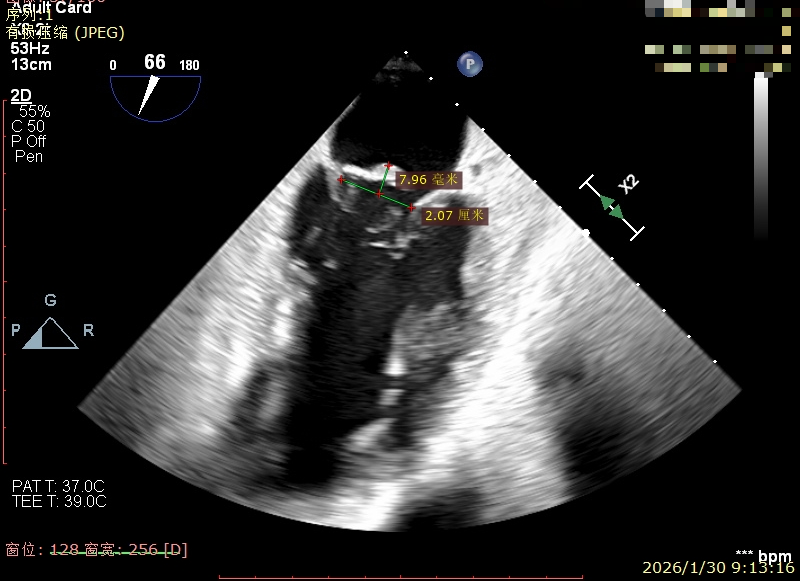

经食道超声精细化测量:肺静脉逆流,房间隔可穿刺高度约4.2cm,Flail宽度约21mm,Flail高度约8mm,Flail Gap约4mm, 3区AML长约23mm、PML长约12mm、2区AML约32.2mm,PML约16mm。

Flail宽度约21mm,Flail高度约8mm